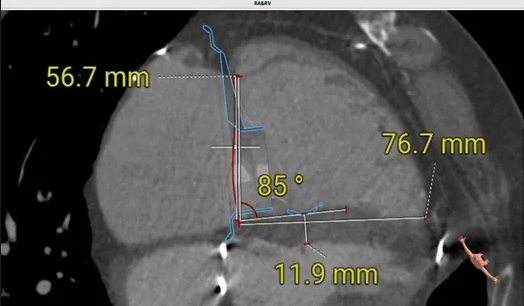

術(shù)前心臟CT評估

三尖瓣環(huán)平均周長徑58.8mm,最大直徑62.2mm

三尖瓣環(huán)切線位夾角 85°